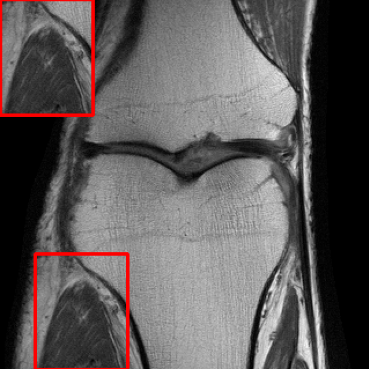

Performance on the Stanford FSE Dataset: We also performed image reconstructions with the Stanford multi-coil FSE dataset, which is a smaller dataset. We used same settings for the networks and training as in Section IV-A. Table III shows that LONDN-MRI significantly outperforms the globally learned MoDL network at both 4x and 8x acceleration. This indicates benefits for the proposed framework for smaller, more diverse datasets. Figs. 7 and 8 display visual comparisons that show the LONDN-MRI scheme recovering sharper features than the globally learned network.

| Ground Truth | Initial | Global | LONDN-MRI | LONDN-MRI | Oracle |

| (1 iteration) | (2 iterations) | ||||

![]() |

| PSNR = dB | PSNR = 19.41 dB | PSNR = 26.52 dB | PSNR = 27.76 dB | PSNR = 27.85 dB | PSNR = 27.92 dB |